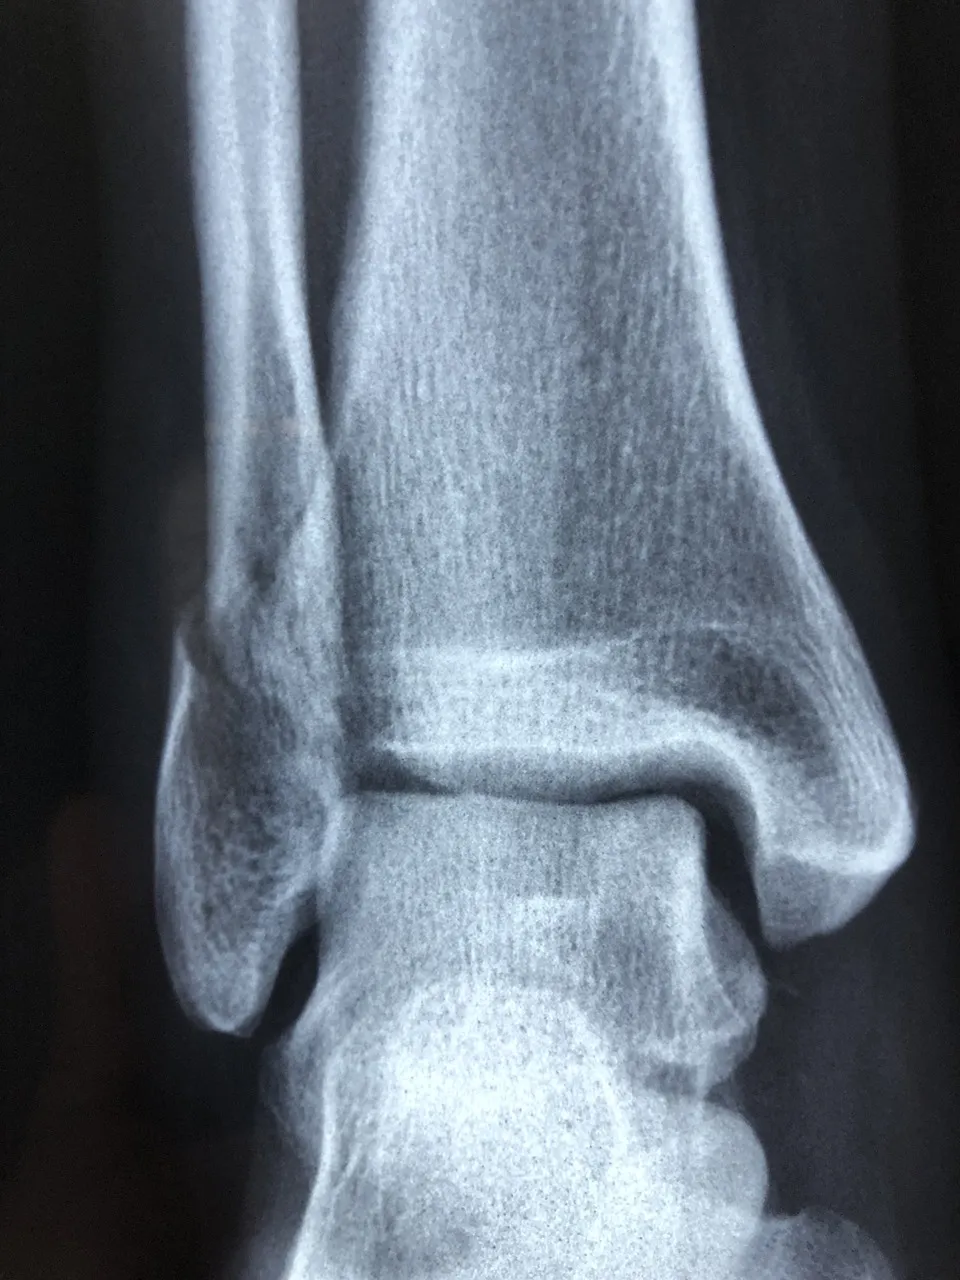

콘드로이친(Chondroitin)은 우리 몸의 연골과 결합조직 속에 자연적으로 존재하는 성분으로

관절 사이에서 충격을 흡수하고 마찰을 줄여주는 역할을 합니다.

나이가 들면서 콘드로이친이 점점 감소하면 관절이 뻣뻣해지고 통증이 생길 수 있다고 합니다.

콘드로이친 효능 2 – 연골 보호 및 재생 도움

콘드로이친은 단순히 통증을 완화하는 것에 그치지 않고,

-연골 세포의 손상을 줄이고 재생을 돕는 역할도 합니다.-

콘드로이친 효능 3 – 관절 윤활 및 유연성 개선

콘드로이친은 관절 속의 윤활 작용을 촉진해 마찰을 줄여주는 역할을 합니다.

실제로 콘드로이친은 관절액의 점도를 높여 유연성을 개선하는 효과가 있다고 합니다.